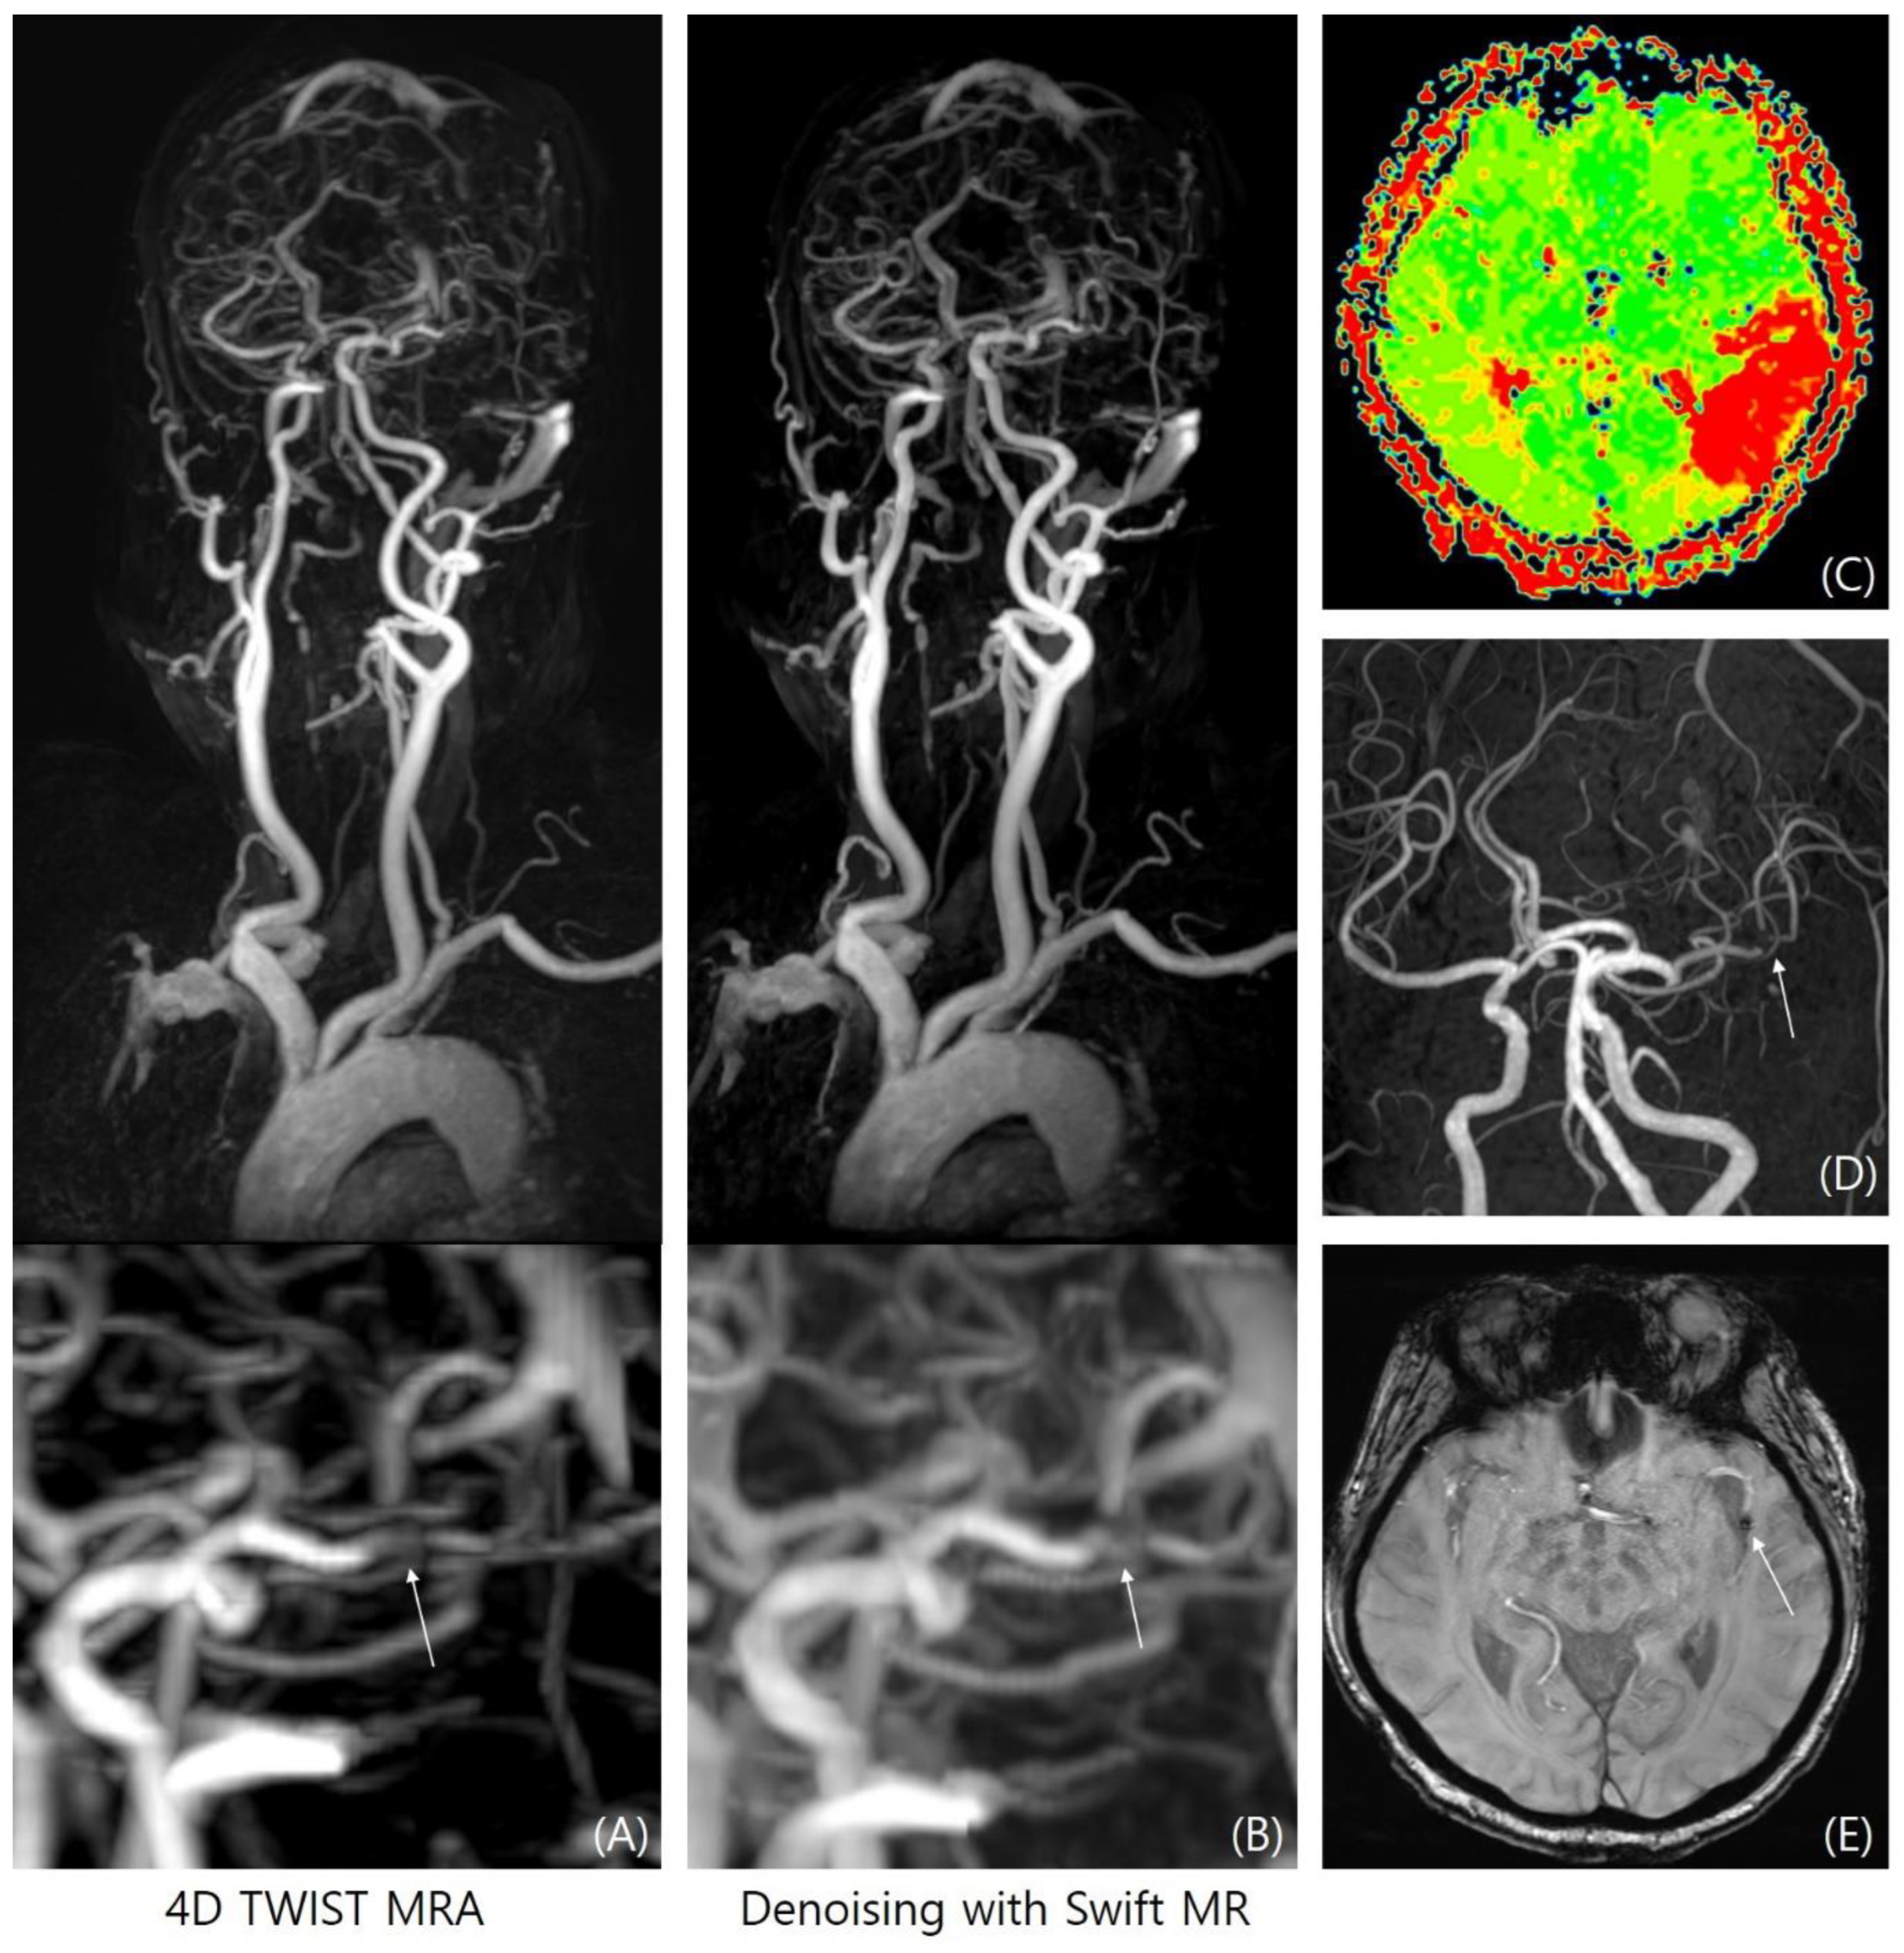

3.2. Aneurysm Detection

3.3. LVO Evaluation

4. Discussion